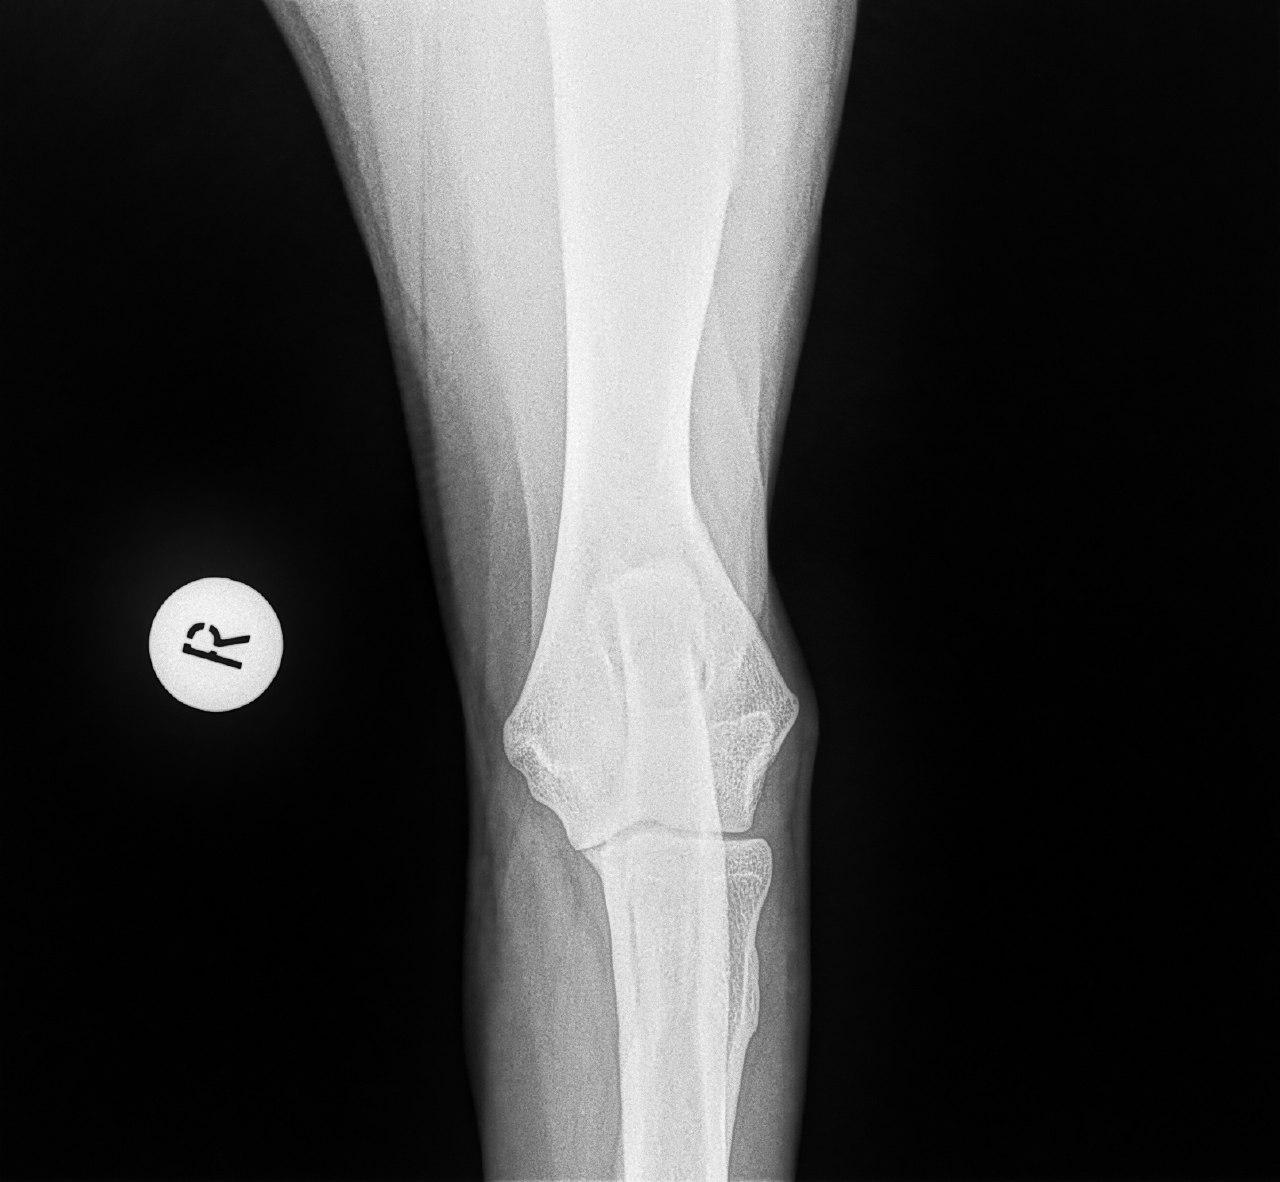

Mit der HD ist das so ne Sache..... die Vererbung spielt eine sehr große Rolle, ja. Aber bei unserer Peggy Zb ist es so, dass mehrere Generationen nachweislich HD und ED frei sind und auch frei von Spondylosen. Als einziger Hund überhaupt in der gesamten Zucht hat unsere Dame alles mitgenommen, was zu kriegen war;(: sie hat nicht nur schwere HD, weil ihre Hüfte viel zu locker ist, sondern dadurch bedingt am rechten Knie bereits schwere Arthrose und hinten links eine Sehenschwäche (durch Überlastung), weshalb sie dort durchtrittig ist. Und als würde das alles nicht schon vollkommen reichen, wurden aktuell auch noch mehrere heftige Spondylosen diagnostiziert;(. An einer Stelle ist sogar schon etwas abgebrochen8|.